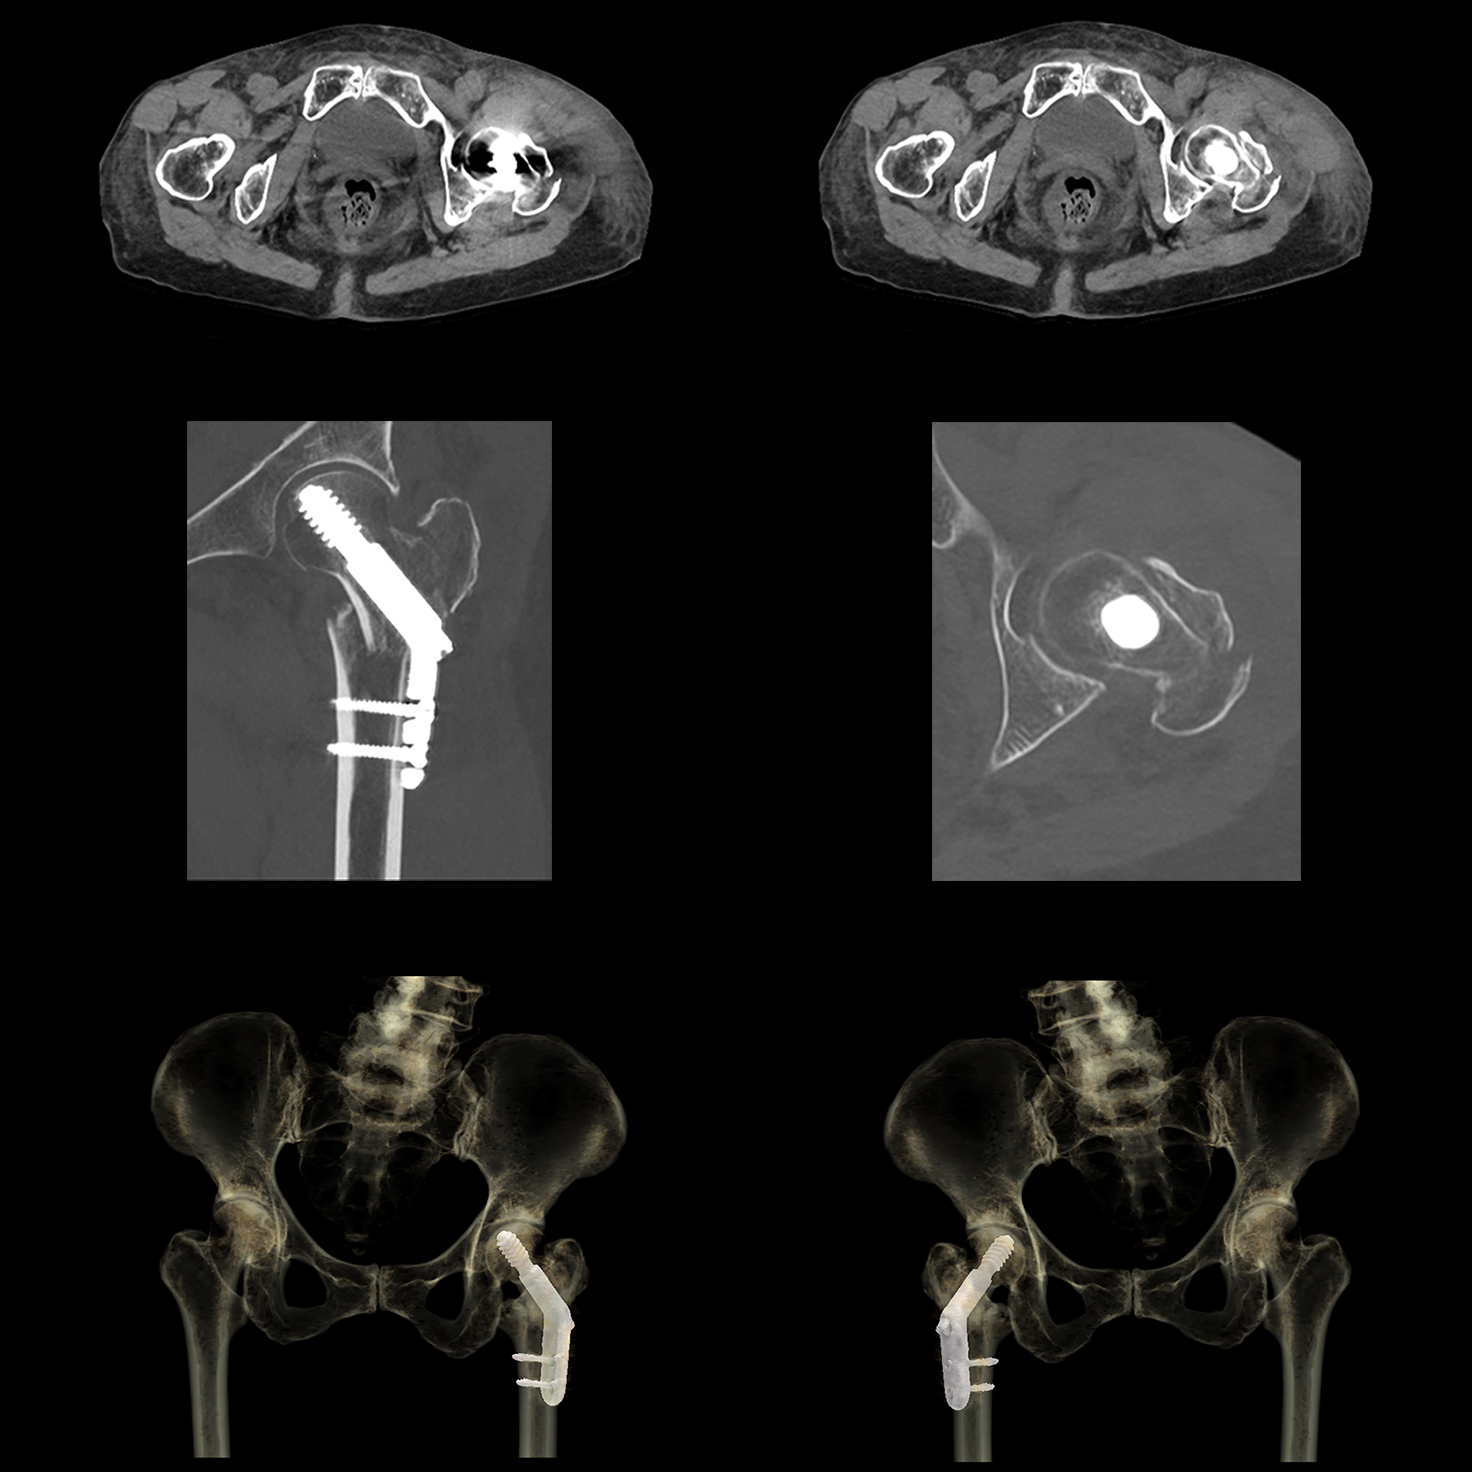

Преодолейте проблемы визуализации коронарных артерий в стентах и сильно кальцифицированных сосудах, объединив мощность однократного сердечного ритма и улучшенную резкость изображения с помощью искусственного интеллекта с PIQE. Реконструкция глубокого обучения со сверхвысоким разрешением PIQE обеспечивает четкие изображения сердца без ущерба для шума, временного разрешения или дозы.

Precise IQ Engine (PIQE)

PIQE обеспечивает улучшенное пространственное разрешение и снижение шума на 45%* для улучшения визуализации в стенте с четким изображением просвета сосуда для оценки неоинтимальной гиперплазии и рестеноза в стенте. Высокая контрастность по сравнению с шумовыми свойствами исследований PIQE также обеспечивает лучшую оценку в сильно кальцифицированных коронарных артериях без потери низкоконтрастной обнаруживаемости* — и эти преимущества обеспечиваются без дополнительной дозы.

Надежные для всех пациентов исследования One beat CTA с PIQE предлагают:

- более четкие анатомические детали,

- уменьшение засветов кальция,

- без дополнительной дозы,

- изофазная однородность.

*по сравнению с AIDR 3D